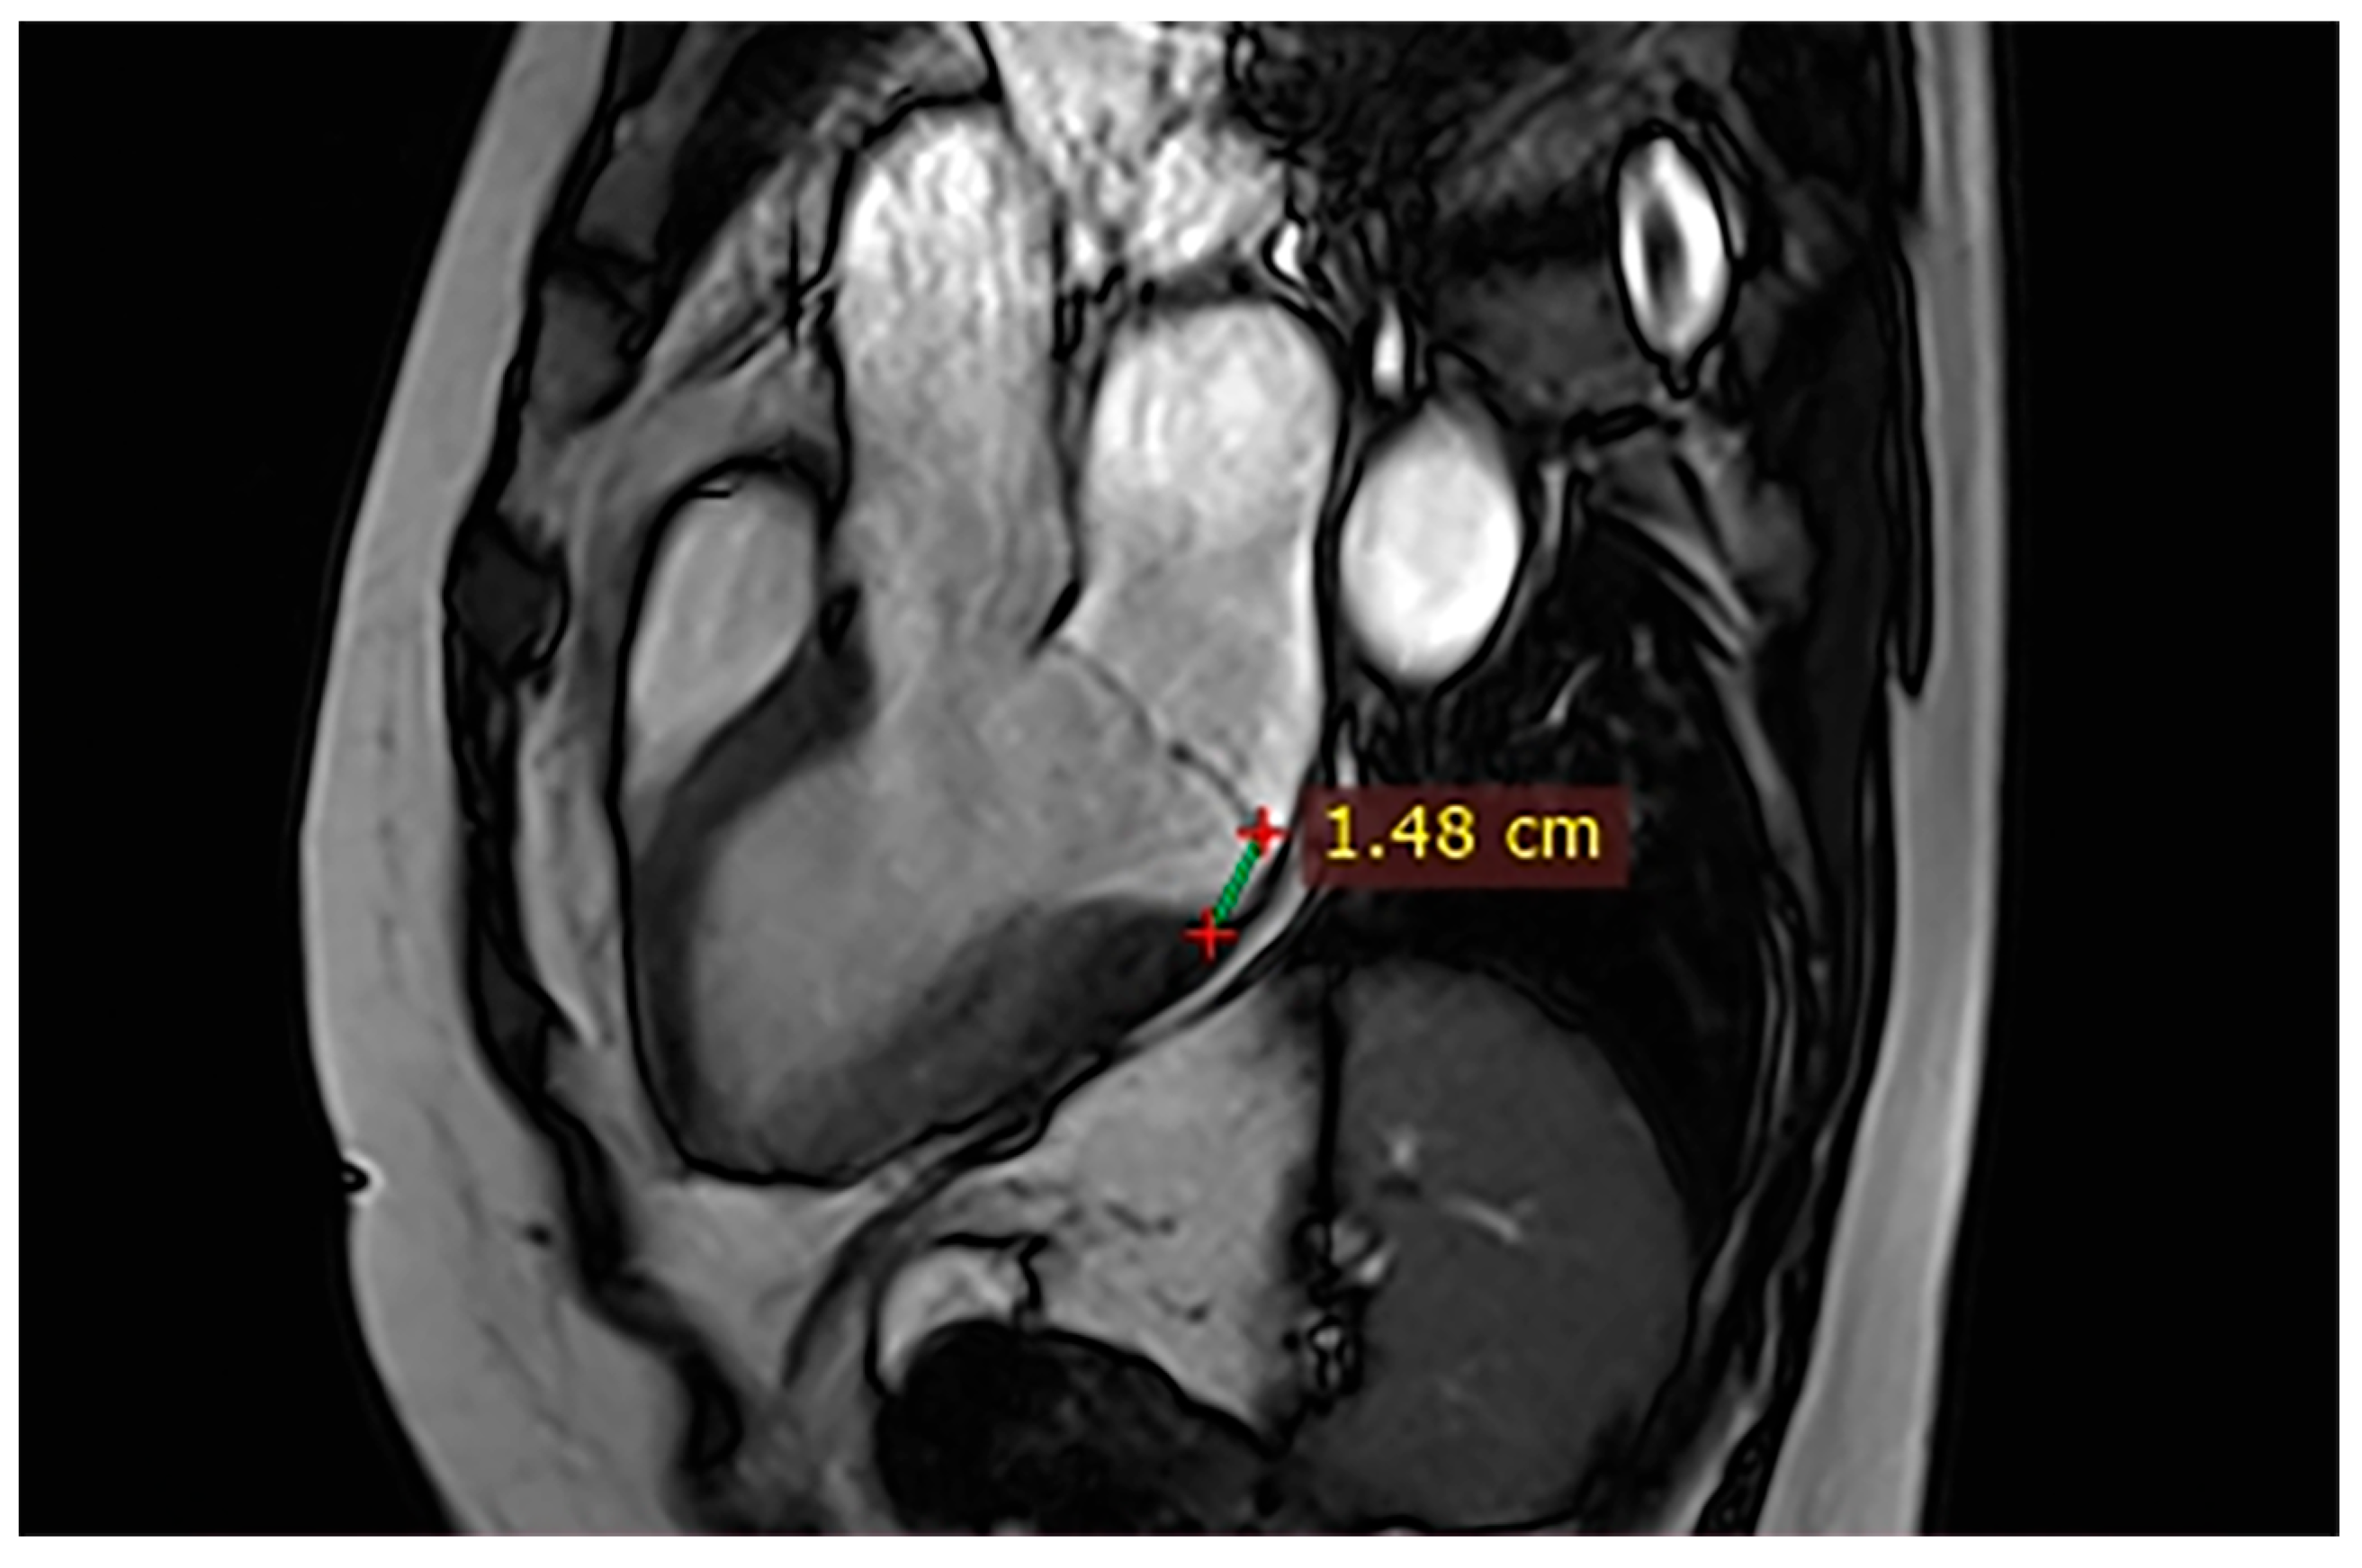

| Case | Patient (Sex, Age) | Symptoms | MAD (mm) | Valvular Issues | LGE | Other Details |

|---|---|---|---|---|---|---|

| 1 | Female, 61 years old | Syncope | 11 | MVP, mitral regurgitation | Lateral | Holter: atrial tachycardia and ventricular ectopy; cardiology follow-up planned for possible mitral valve repair |

| 2 | Male, 52 years old | Syncope and atypical chest pain | 10 | - | Lateral | History of ventricular arrhythmias; cardiology follow-up and Holter monitoring recommended |

| 3 | Female, 74 years old | Extrasystole | 3 | - | No LGE | No LGE; patient reassured and scheduled for periodic clinical follow-up |

| 4 | Male, 34 years old | Extrasystole in Marfan syndrome | 15 | MVP, valvular regurgitation | No LGE | Marfan syndrome; MVP with regurgitation; regular cardiology follow-up advised. |

| 5 | Male, 63 years old | Heart failure | 2,5 | MVP, valvular regurgitation | No LGE | Reduced LVEF (47%) with left atrial dilatation; heart failure therapy optimized; follow-up planned. |

| 6 | Male, 68 years old | Palpitations | 5 | - | Lateral | LGE in basal lateral wall; electrophysiological evaluation and ECG monitoring recommended. |

| 7 | Female, 53 years old | Extrasystole and syncope | 15 | MVP, valvular regurgitation | Basal-lateral | Extensive MAD with MVP and LGE; increased arrhythmic risk; antiarrhythmic therapy considered. |

| 8 | Female, 63 years old | Aortic and mitral regurgitation | 11 | Aortic and mitral regurgitation | Lateral | Aorto-mitral regurgitation with septal hypokinesia; mitral valve repair performed; heart failure therapy started. |

| 9 | Male, 45 years old | Palpitations and vertigo | 10 | - | Lateral | Basal lateral LGE; regular clinical and ECG follow-up recommended |